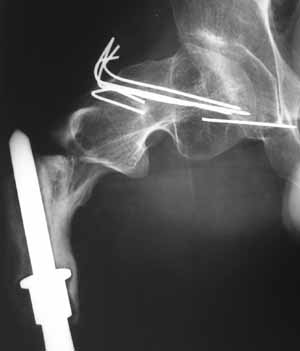

В 1998 году - перелом шейки бедра- оперирован в детской больнице (остеосинтез пучком спиц). В 2001 году- подвертельный перелом (полгода в коксите- сращение). В марте этого года- повторный подвертельный перелом (см RG). В настоящее время в коксите. Что дальше? Облздрав выделяет на лечение чуть более 100 тыс руб. (квота) Может кто-нибудь помочь пациенту? С уважением Ганин Алексей.

In 2001 subtroch fracture, 6 months in plaster casr - healing was reached.

March 2004 - a new fracture at the place, images attached. Now the patient is in the cast again.

A cable plate could provide stabilization of the remaining fractured proximal femur. Fixed angle device proximally (blade, screw or locking plate) with distal fixation of the plate to the bone/bone replacement prosthesis by means of cables. If there is bone in the subtrochanteric region (hard to see on the radiographs) then unicortical screws might also be possible. Of course, remove the wires in the femoral neck and head.

Создается впечатление, что причиной повторного подвертельного перелома бедра является нестабильность протеза( сложно судить о тибиальном компоненте по Рг грамме, но видимая часть бедра - на всем протяжении зона остеосклероза с истончением кортикала) Нестабильное *железо* вызывает резорбцию кости, ее ослабление и как результат -перелом ( обычно на уровне верхушки ножки протеза - зона стресса).

Согласен с Александром, что для фиксации такого перелома невозможно найти стандартное решение. Идея интрамедуллярной фиксации заманчива, но технически трудновыполнима (опил и сверление стержня протеза+ нарезка резьбы.....) и сомнения в плане окончательной стабильности фиксации, коль скоро сам бедренный компонент нестабилен.